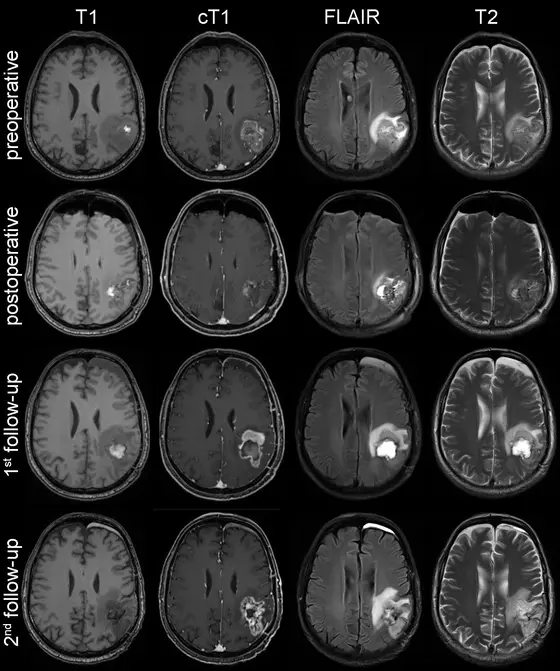

MRT-Aufnahmen im Verlauf der Erkrankung bei einem Patienten mit Glioblastom